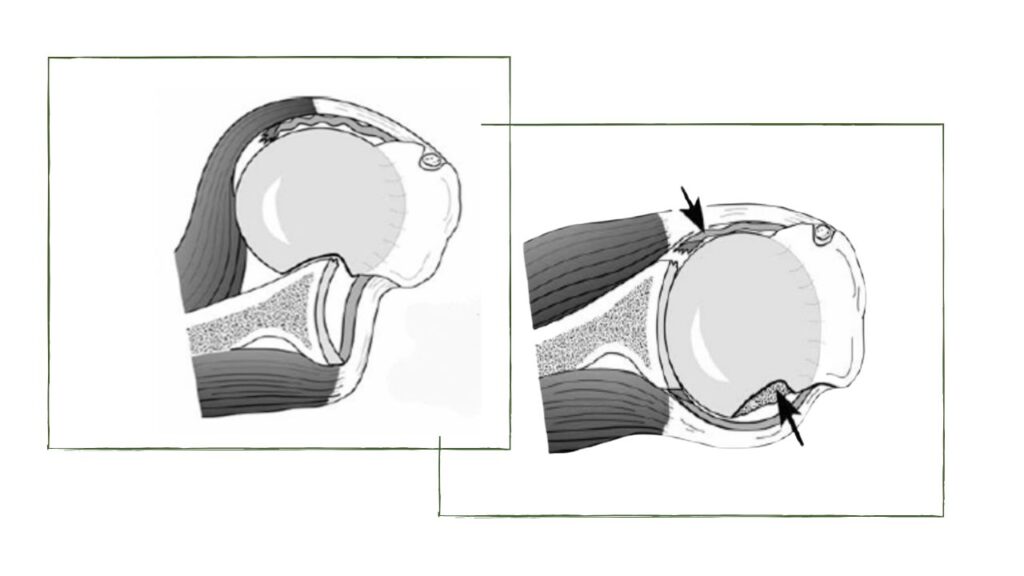

Quando ocorre a patologia e ocorrência de luxação, um ou mais estabilizadores se tornam insuficientes. No trauma em que o braço é forçado em uma posição abduzida e rodada externamente, o achado característico é a lesão labral de

Bankart e da correspondente lesão da cabeça umeral de Hill Sachs. Outros fatores importantes são a capsula articular mais frouxa e redundante e a lesão acumulativa por micro traumas de repetição, as chamadas lesões por overuse.

Por meio do diagnostico por imagem, no exame de Ressonância ou Tomografia, são traçadas linhas para a medida do acometimento ósseo tanto do osso glenóide (Bankart ósseo) quanto do correspondente Hill Sachs da cabeça umeral, e a soma das medidas vai recomendar a cirurgia mais efetiva para o caso avaliado. No entanto, este conceito também depende da experiência, da escola do cirurgião, da atividade esportiva do paciente, do número de luxações e se é uma primeira cirurgia ou uma recidiva.